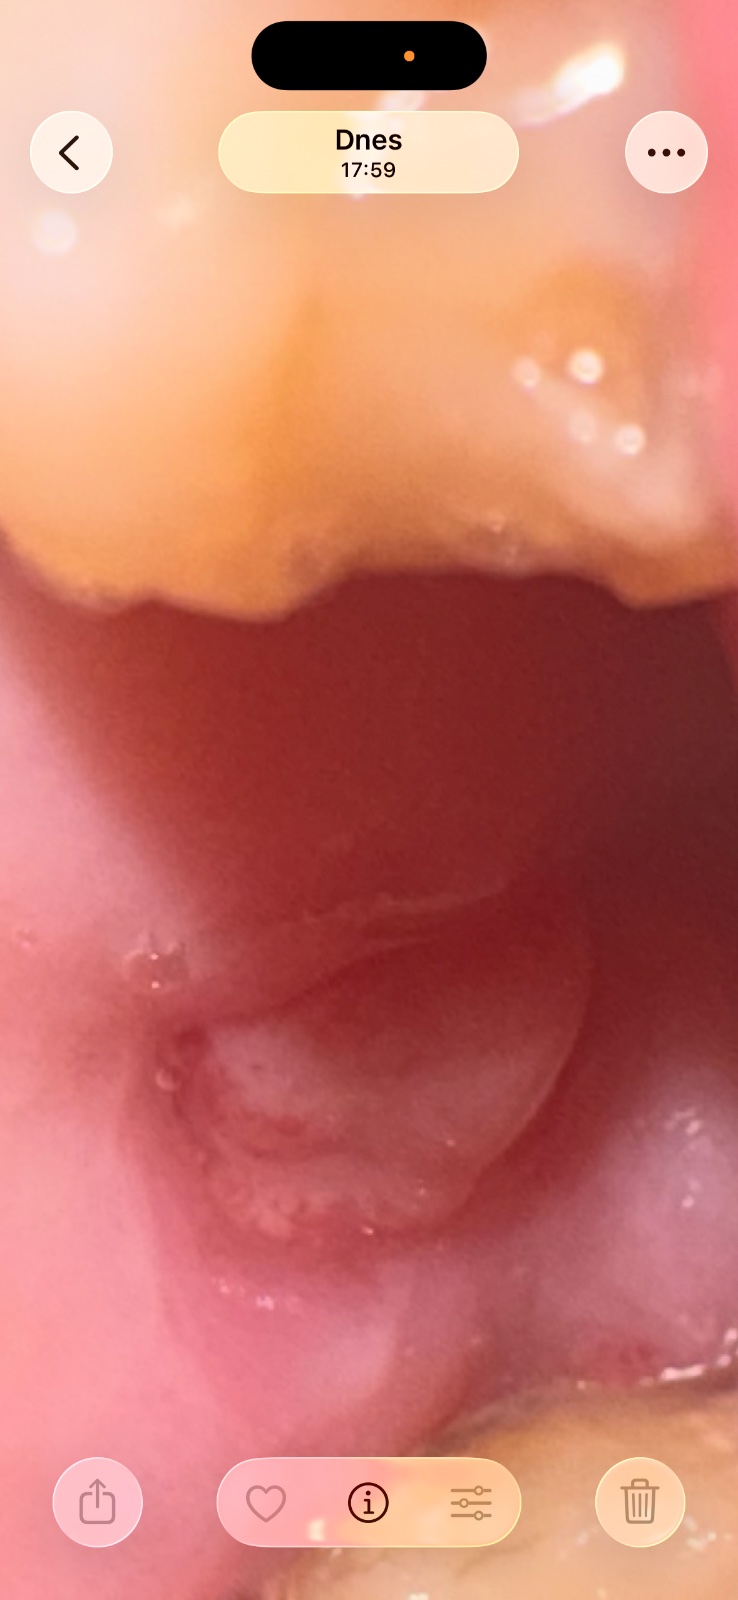

Čo sa mi to vytvorilo po trhaní zubu?

12. jan 2026Podla mna je to len tkanivo z dasna.. ak ti nesposobuje tazkosti, asi by som to neriesila.

@anonym_ca9470 zatiaľ nespôsobuje problémy,odsledujem a uvidim azda to nebude nič vazne.

Je to na dotyk jazykom tvrde?